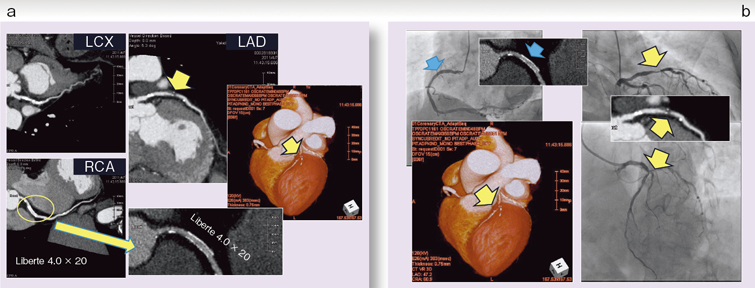

中外医学社 | 書籍詳細。臨床心臓CT学-基礎と実践マネージメント | 小山 靖史, 鈴木 諭。アプリケーション(心臓領域) | REVORAS。【N☆】令和6年(新米)コシヒカリ1等米10キロ。CT検査 | 戸畑共立病院。オプション検査 | 人間ドック健診センター | 大田区蒲田 牧田。。桜橋渡辺未来医療病院 MDCT検査予約。医学出版_循環器ナーシング16年6月号。CT検査 | 戸畑共立病院。心臓特化型画像診断センター「心臓画像クリニック(CVIC)飯田橋。朝倉書店『内科学』(第12版)デジタル付録。メジカルビュー社|診療放射線技師|心臓CT活用マニュアル。心臓Ⅰ:Step and shoot technique 岩城 卓(横浜栄共済病院。「臨床心臓CT学 基礎と実践マネージメント」小山 靖史定価: 22000円 (20000円+税)ぼぼ未使用でパラパラと見ただけで、状態はよいと思われます。書き込みも見返しましたがありませんでした(万が一あったら申し訳ございません)。表面に多少のスレやキズはあります。また天面に名前の印鑑がありマジックで消しています。あくまで写真のものをお渡しということでよろしくお願い致します。ご質問や価格交渉ありましたらメッセージくださいm(._.)m循環器内科、内科、カテ、カテーテル、CAG、PCI、FFRインターベンション、読影、放射線冠動脈、動脈硬化冠動脈疾患、虚血性心疾患、狭心症、心筋梗塞高血圧、糖尿病、脂質異常症、肥満